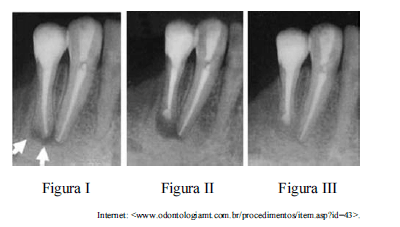

Um paciente do sexo masculino, de quarenta e seis anos de idade, procurou atendimento odontológico por motivo de presença de fístula recorrente, havia seis meses, na região anterior inferior. O paciente relatou, ainda, ter tratado canal nos elementos 43 e 44 havia cerca de dez anos.

Considerando as imagens radiográficas como referência, nas quais as setas indicam presença de alteração periapical, julgue os itens subsecutivos a respeito do caso clínico apresentado.

No caso desse paciente, o planejamento de uma microcirurgia endodôntica para curetagem com a amputação do ápice radicular (figura II) dispensa a etapa de retratamento endodôntico em razão da realização da obturação retrógrada da raiz com material dotado de atividade antimicrobiana.